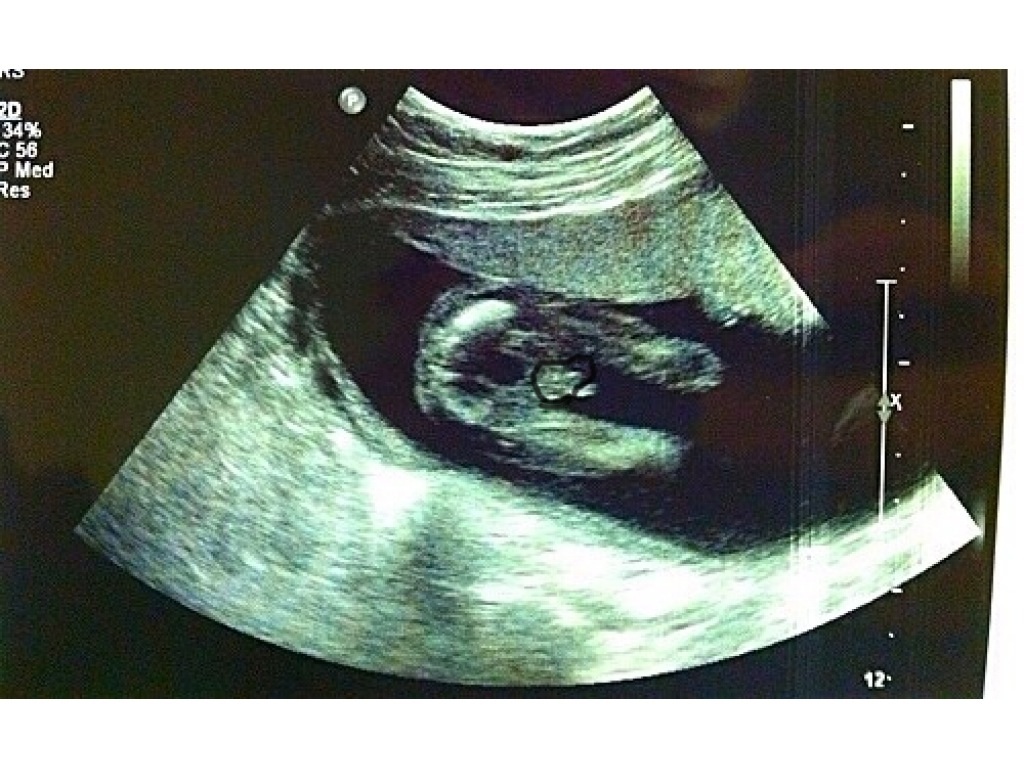

Attachment 13543I thought this was a girl but apparently. a boy completely threw me, (not my scan)

Yes, that's a boy.

It's not a great scan for either gender (but is a nice bladder shot). It does appear more boyish, though.

It looks like clear scrotum and penis to me.

I don't know what that forked thing is but just below it is the penis